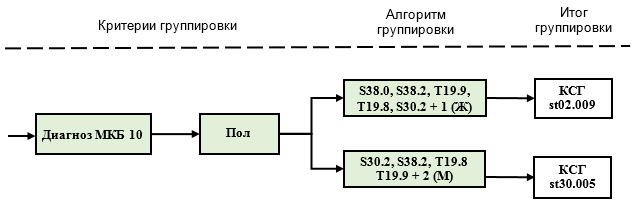

| S30.2 | 2 | st02.009 | |||||

| T19.8 | 1 | st30.005 | |||||